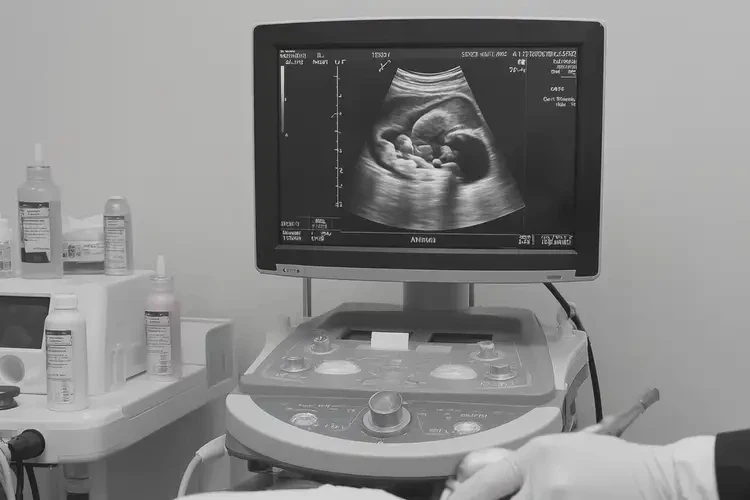

- 超声检查:医生会进行超声检查,以评估胎儿的发育情况和是否存在结构异常。